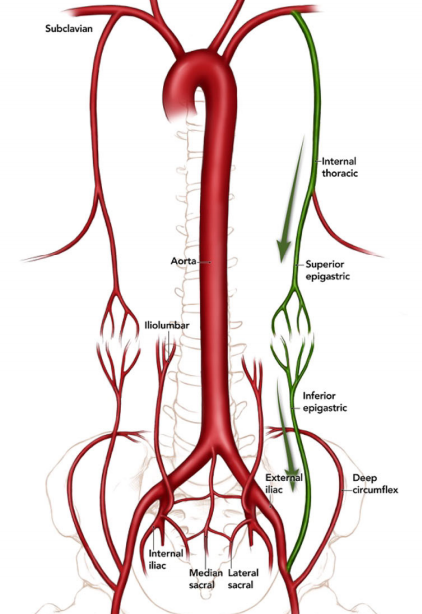

Collatérale de Winslow

- Voie de dérivation lors d’occlusion de l’artère iliaque externe

- Entre l’artère épigastrique supérieure et inférieure

- Subclavière → Mammaire interne → Epg-Sup → Epg-Inf → Iliaque Ext